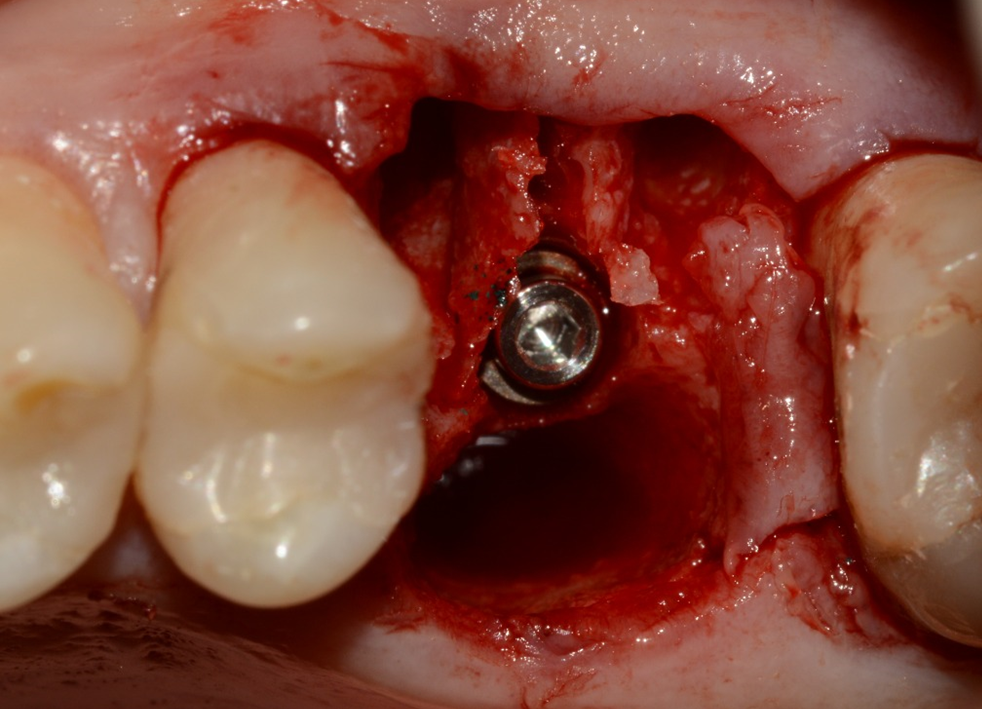

A sequência de imagens a seguir apresenta casos da aplicação clínica do Extra Graft em cirurgias de exodontia e implante imediato com preenchimento dos gaps, e apenas exodontia e preenchimento alveolar para favorecer a regeneração óssea.